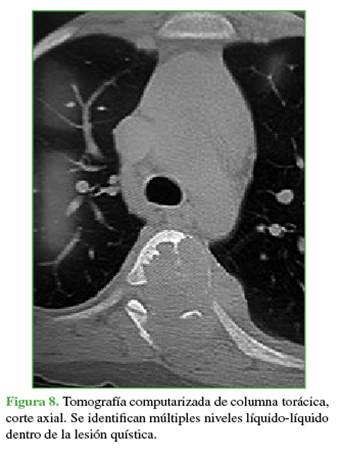

La zona afectada era 3-6, niveles III y IV de la clasificación de Weinstein-Boriani-Biagini.11 En los estudios complementarios, se observaron múltiples quistes tabicados con niveles líquido-líquido, por lo que se descartó un quiste óseo simple, de características expansivas y compresivas, ante este patrón se descartó la posibilidad de un hemangioma vertebral (Figuras 7 y 8). Este caso también se interpretó como una lesión secundaria a un QOA grado 3 de Enneking.13

Las radiografías, la tomografía computarizada y la resonancia magnética son los estudios complementarios que ayudan a llegar al diagnóstico. En las radiografías, se observa una cavidad expansiva osteolítica. En la tomografía y la resonancia, se visualizan los característicos niveles líquido/líquido.8